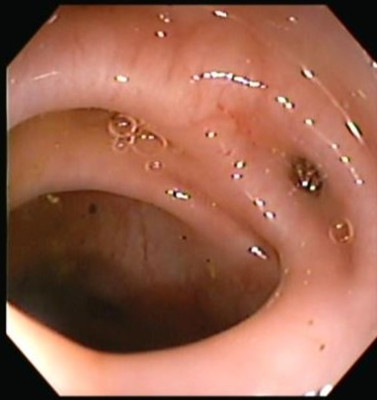

Enfermedad diverticular del colon

Envíado por Dr. Carlos Ernesto Arévalo